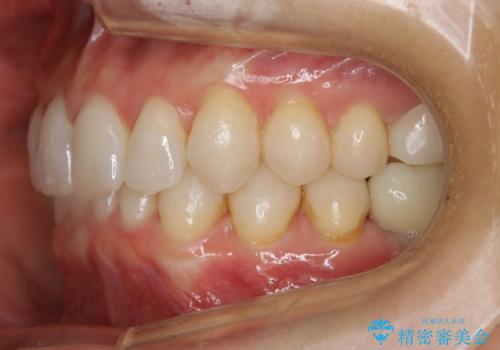

【抜歯】矯正治療とインプラントで正常な噛み合わせを実現

- 元々は矯正治療を主訴にご来院されました。

治療を始めるにあたり、精密検査を受けていただき全体の状況を把握したうえで矯正治療の計画を立てることとなりました。

その過程で左下の6番目の歯は治療が必要な状態であることが分かり、被せ物を外して内部を確認してみると根が破折してしまっていることが判明しました。

歯が深い位置で破折している場合は基本的には抜歯が選択されます。

様々な治療プランを患者さんと相談させて頂き、最終的にインプラントで噛み合わせを回復させていくこととなり、まず悪くなっている歯を抜歯することから開始しました。